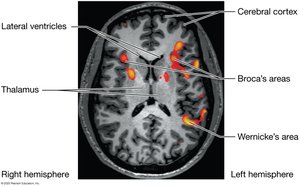

Broca's area (frontal lobe) produces language; Wernicke's area (temporal lobe) understands language. Damage results in aphasia.